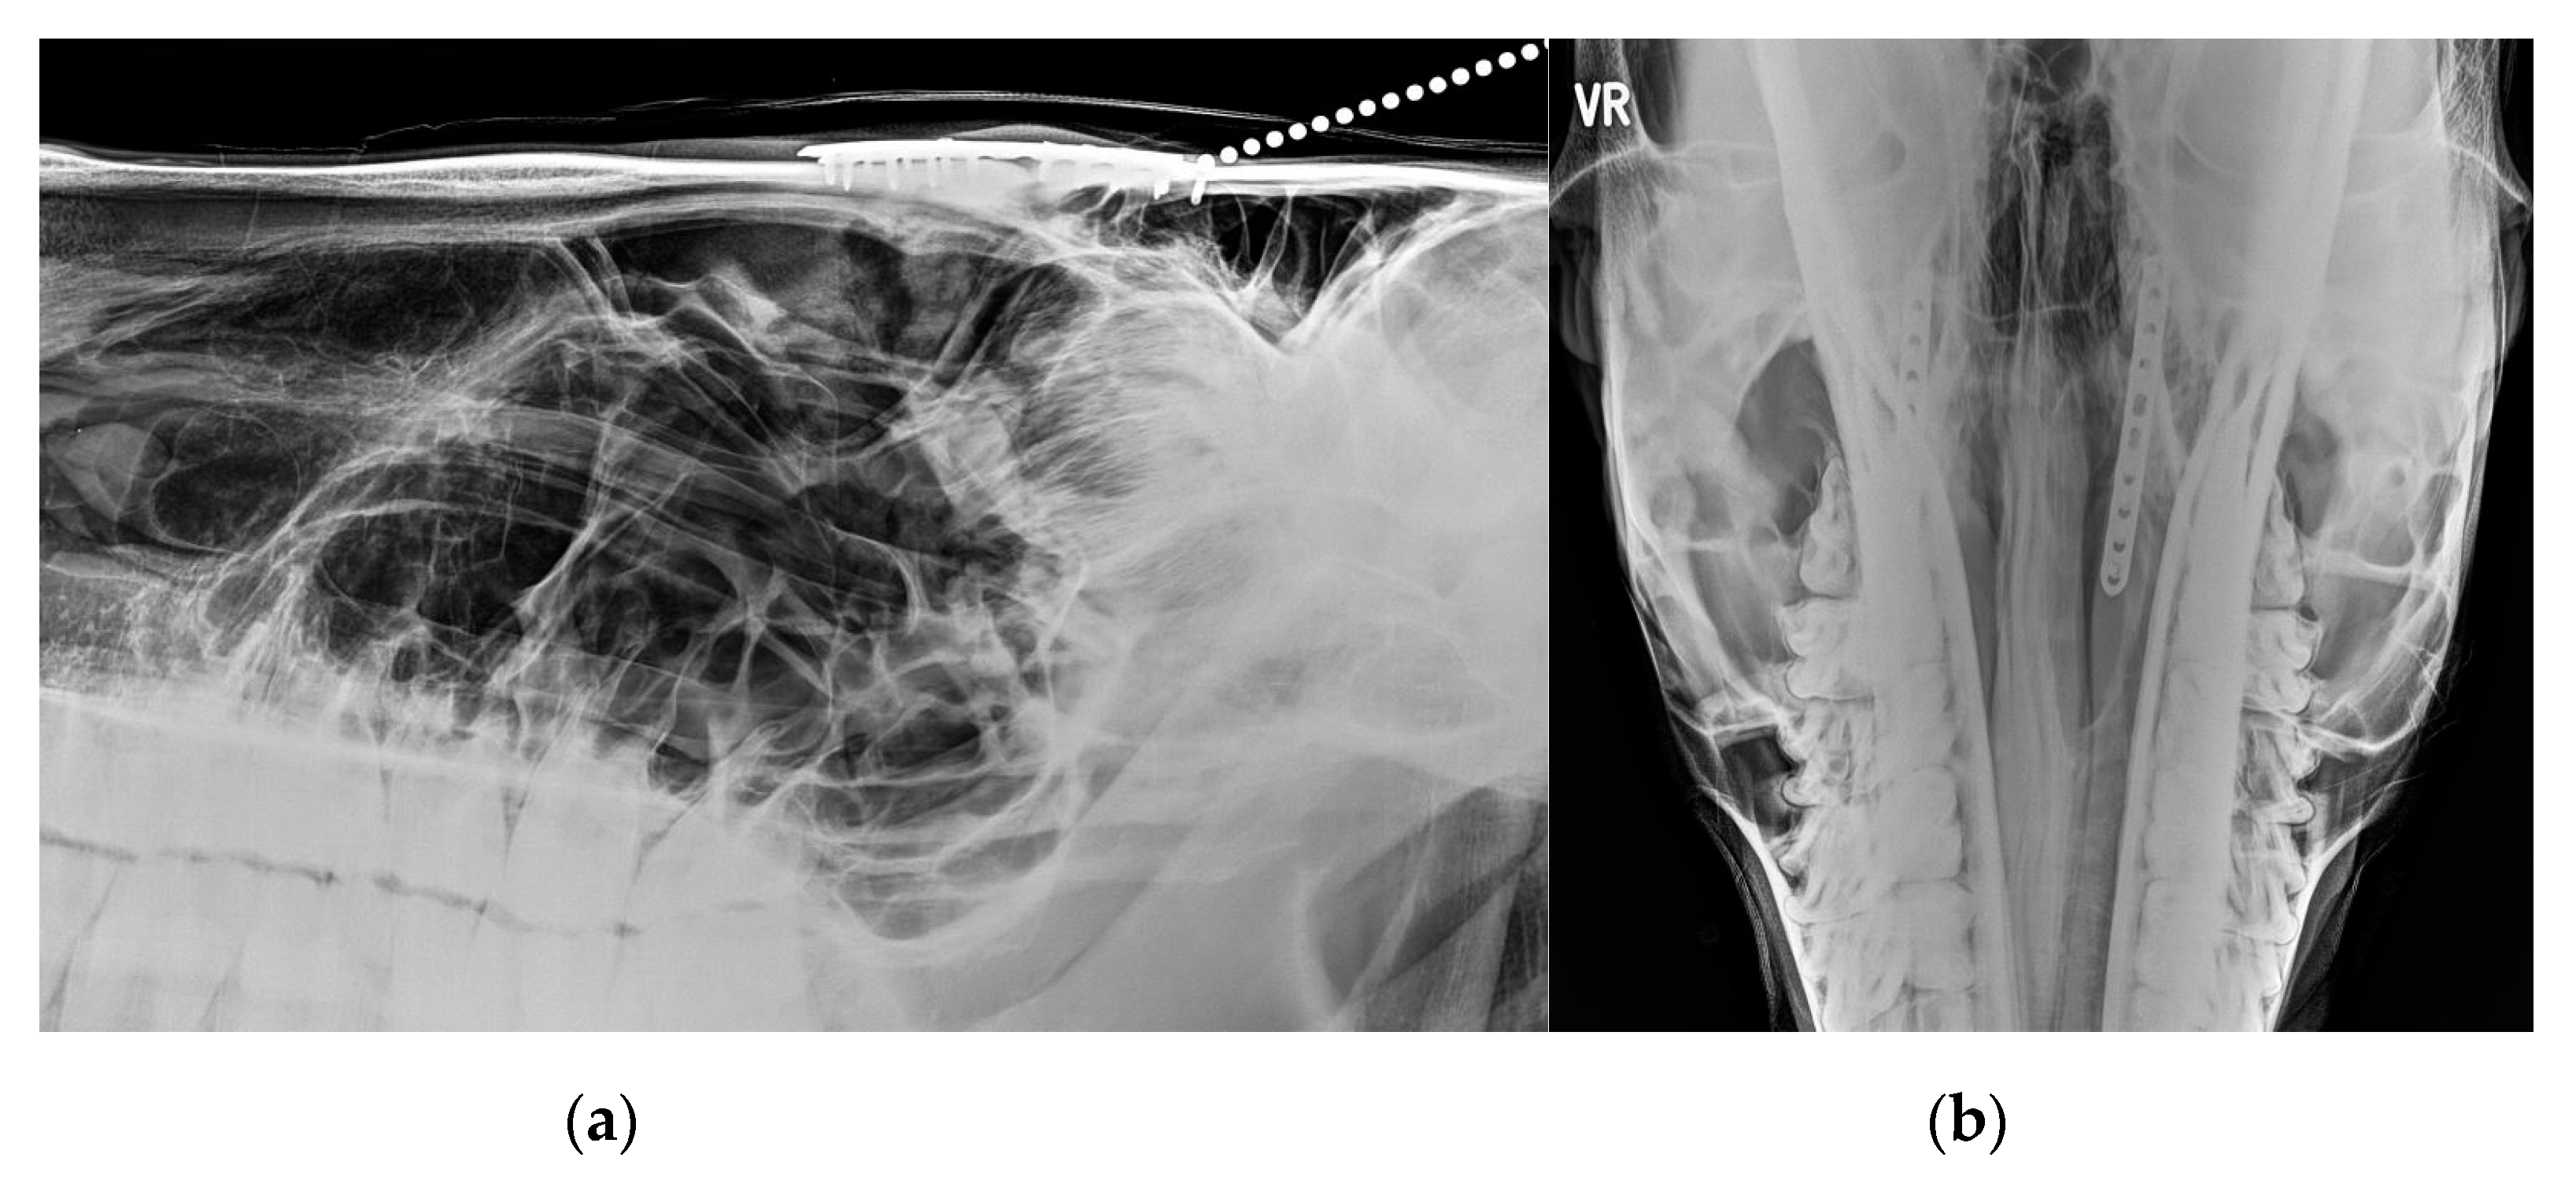

3.2. Imaging Findings